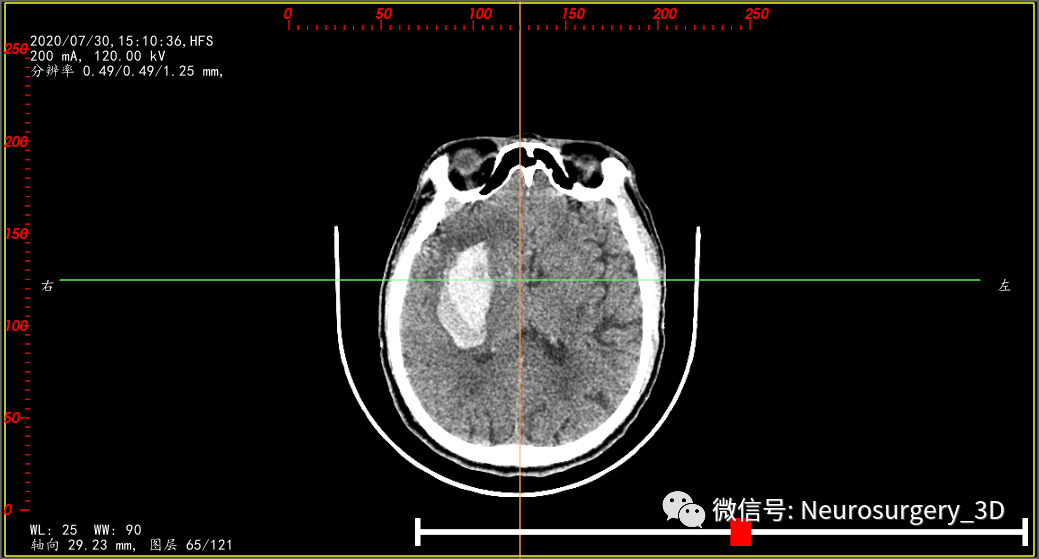

为了验证是不是活动性出血,再次复查颅脑CT(2020年7月30日15:10)如下:两次CT(间隔约6小时)对比,血肿形态无明显变化,证实并非活动性出血。

两种治疗方案截然不同,只有精准判断出出血类型,恰当选择治疗方法,术后效果立现。该病例我们首选微创钻孔置管引流术,为了把引流管精准的置入到低密度液态血肿部分,我们设计引流管顺血肿长轴进行,并把靶点置入到血肿中后1/3处,先引流液态血肿减压,再应用尿激酶液化高密度血肿部分。